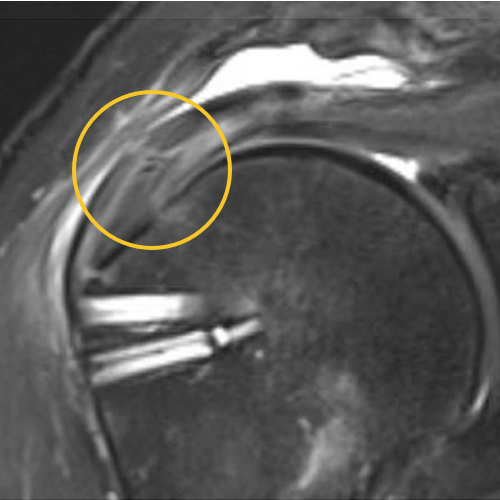

This is one of my cases, a 55-year-old woman, when her primary rotator cuff repair was done, we used Dermis on Demand, which is an allograft skin that can be utilized to help strengthen repairs. At four months out, the patient presented with pain and weakness following a traumatic injury and wound up re-tearing.

You can see a clear retear to the rotator cuff here with slight retraction, and some degeneration and thickness to the tendon.

This was not a softball case. Many aren’t. These are the complex rotator cuffs that worry you at night... Are you going to be able to fix it? Yes. But will it heal? That's the challenge. And that's where this implant helps you on a day-to-day basis.

We published this case study in the JOEI (Journal of Orthopedic Experience and Innovation) Journal. We did a revision of the large type-II repair and augmented it with BioBrace®. You can see the pre-op and three-month MRI below. Still fluid in the subacromial space but that tendon is clearly coming across into the footprint. Then, an eight-month MRI shows there's no further fluid in the subacromial space and maturation of that repair across the footprint.